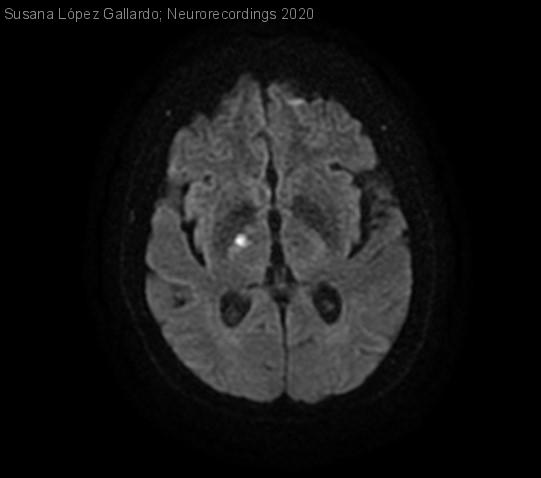

Diagnóstico final: Hemicorea izquierdo de inicio agudo secundaria a ictus isquémico talámico derecho

-Un año antes valorada por Neurología por mareos e inestabilidad con lateropulsiónderecha. RMN cerebral: leucoencefalopatía vascular isquémica de pequeño vaso cerebral, hallazgos que probablemente corresponden a patología crónica por HTA.